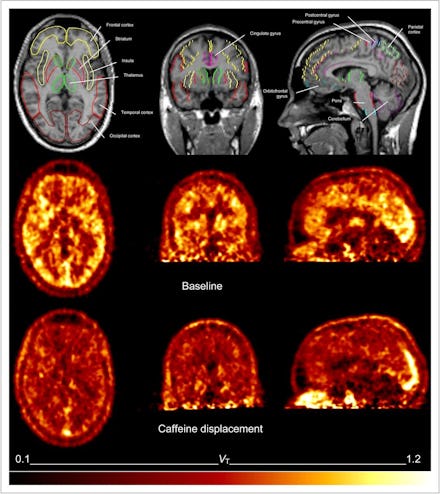

This image was taken from a study on methods of studying caffeine's effect on the brain, and should not be interpreted as "caffeine's effect on the brain."